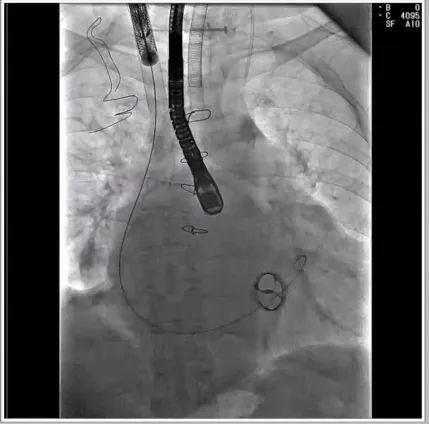

根据术前评估结果,郭应强教授团队为患者量身定制了手术策略,决定使用LuX-Valve Plus经血管三尖瓣置换系统开展手术治疗。手术在全麻下进行,采用经右侧颈静脉入路,在经食道超声和DSA的指引下调整输送器角度以达到正确位置,勾住前瓣后逐步释放盘片,盘片打开后顺利扎针,最终完成瓣膜植入,输送器撤出。术后超声提示人工三尖瓣同轴性良好,瓣架固定牢靠,无反流和瓣周漏,术后三尖瓣平均跨瓣压差为1 mmHg。

术后DSA造影